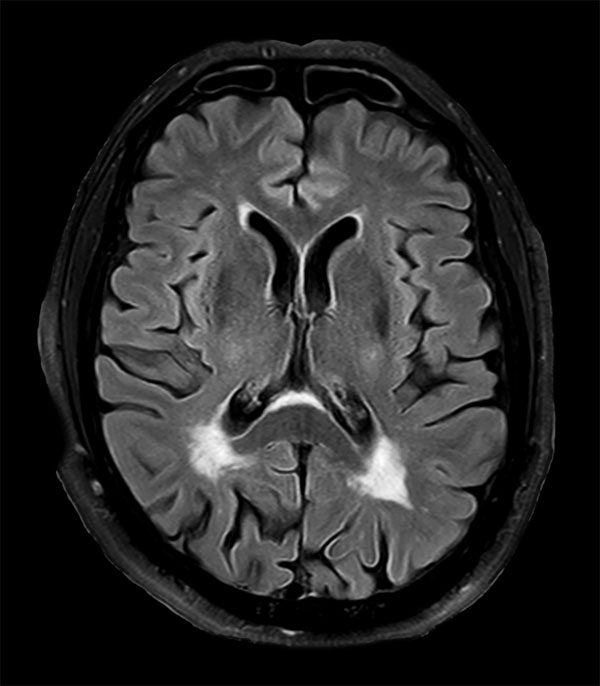

76-year-old male with history of amyloid angiopathy. Sagittal T1-weighted images shows chronic deep white matter ischemic changes. Axial T2-weighted and FLAIR demonstrate chronic ischemic changes and old hemorrhage / hemosiderin staining. Axial Venous BOLD (Susceptibility Weighted Imaging) image show chronic ischemic changes and old hemorrhage / hemosiderin staining. Imaging appears consistent with amyloid angiopathy, no other intracranial lesions are found.

Axial 3D FLAIR